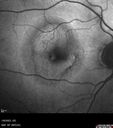

80 year old patient with HemiCRVO and wet AMD in the left eye. The right eye has recent vision loss from 20/40 - 20/100. She has a high PED and wet AMD. She was given one treatment of half-dose vabysmo and presented next visit with a PED tear and vision of 4/200.

RPE tear following single treatment of vabysmo in the left eye216 views80 year old patient with HemiCRVO and wet AMD in the left eye. The right eye has recent vision loss from 20/40 - 20/100. She has a high PED and wet AMD. She was given one treatment of half-dose vabysmo and presented next visit with a PED tear and vision of 4/200.00000